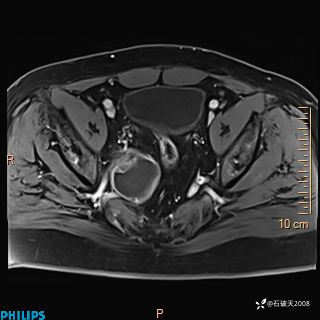

2023年3月份MRI影像

增强轴位